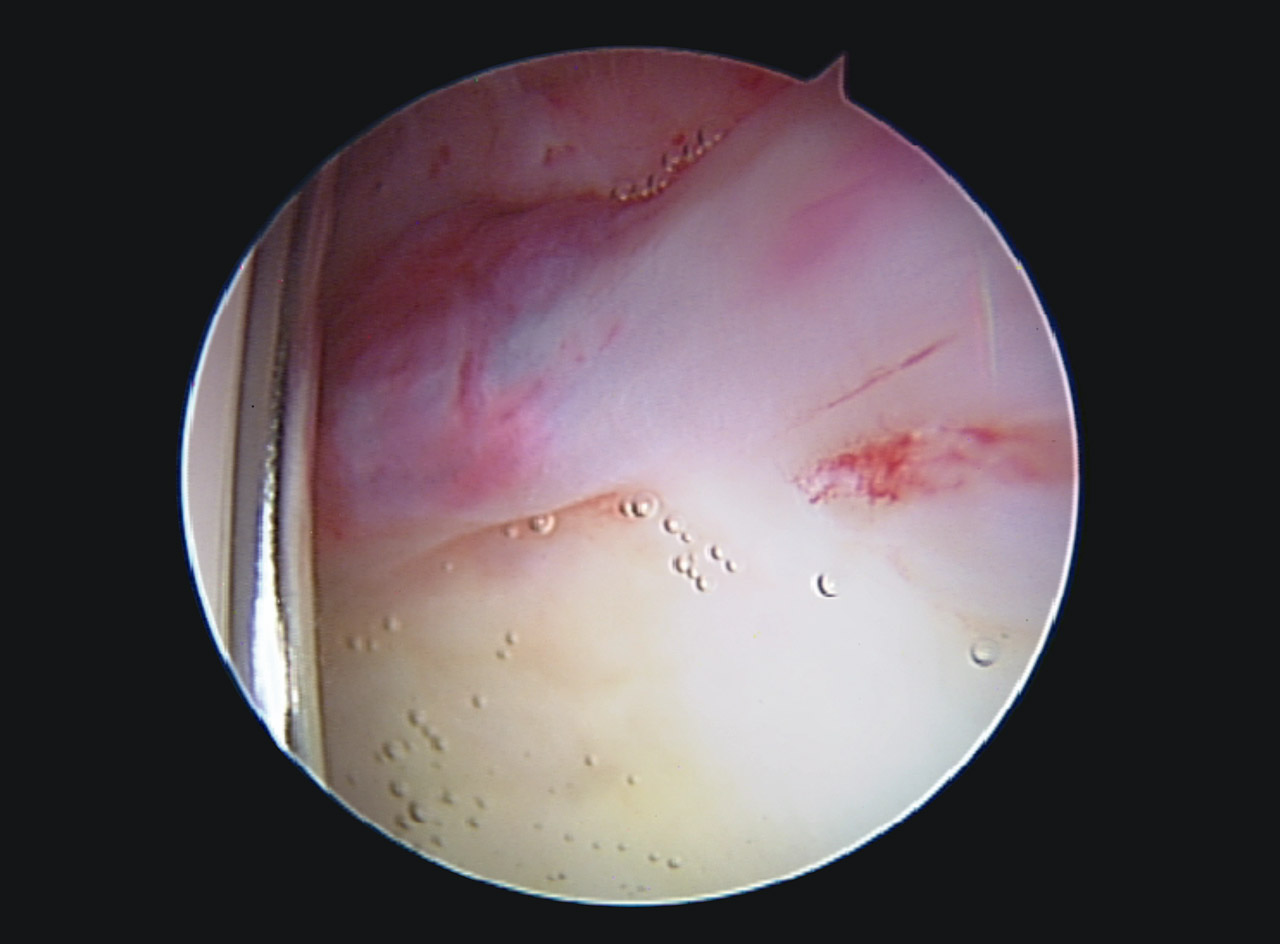

En la exploración artroscópica se observó un labrum hiperémico en la región anteroexterna, con un aumento del tejido sinovial adyacente al labrum. Se realizó una destrucción de dicho tejido mediante el uso de un vaporizador de radiofrecuencia, tal y como se observa en las Figuras 3 y 4. El complejo condrolabral se encontraba conservado y no requirió reanclaje.

En vista de su evolución, se decidió realizar una cirugía artroscópica de cadera derecha bajo la sospecha de AFA sin signos radiológicos. La imagen artroscópica mostraba un labrum hiperémico con una zona anterosuperior con rotura condrolabral y lesiones cartilaginosas acetabulares de tipo ALAD 1 con wave sign presente (Figura 7). Se realizó una sinovectomía local con vaporizador de radiofrecuencia y reanclaje labral mediante sutura.